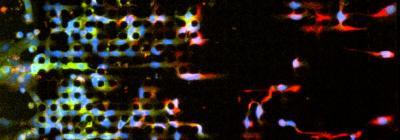

As cells undergoing the epithelial-mesenchymal transition move from left to right through the EMT chip, those expressing mesenchymal markers (red) break away and move independently from other cells, while cells expressing epithelial markers (green) continue to move as a collective front.

(Photo Credit: BioMEMS Resource Center, Massachusetts General Hospital)

When cells in which the process of EMT had been initiated by genetic manipulation were observed passing through the device, at first they migrated collectively. But soon after encountering the first micropillars, many cells broke away from the collective front and migrated individually for the rest of their trajectory. Some cells appeared to undergo the opposite transition, reverting from individual migration back to collective migration. Subsequent analysis revealed that the slower moving cells that continued migrating together expressed epithelial markers, while the faster moving, independently migrating cells expressed mesenchymal markers. The individually cells migrating also appeared to be more resistant to treatment with chemotherapy drugs.